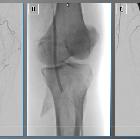

graft for arterial injury management: safety, technical success, and long-term outcome. Viabahn stent graft for endovascular rupture treatment. A 52-year-old male reported experiencing leg pain following a work-related accident at a construction site. A Angiogram revealed traumatic rupture of the popliteal artery (blue arrows). B A Viabahn stent graft was deployed. C Final target site angiography demonstrated restored blood flow